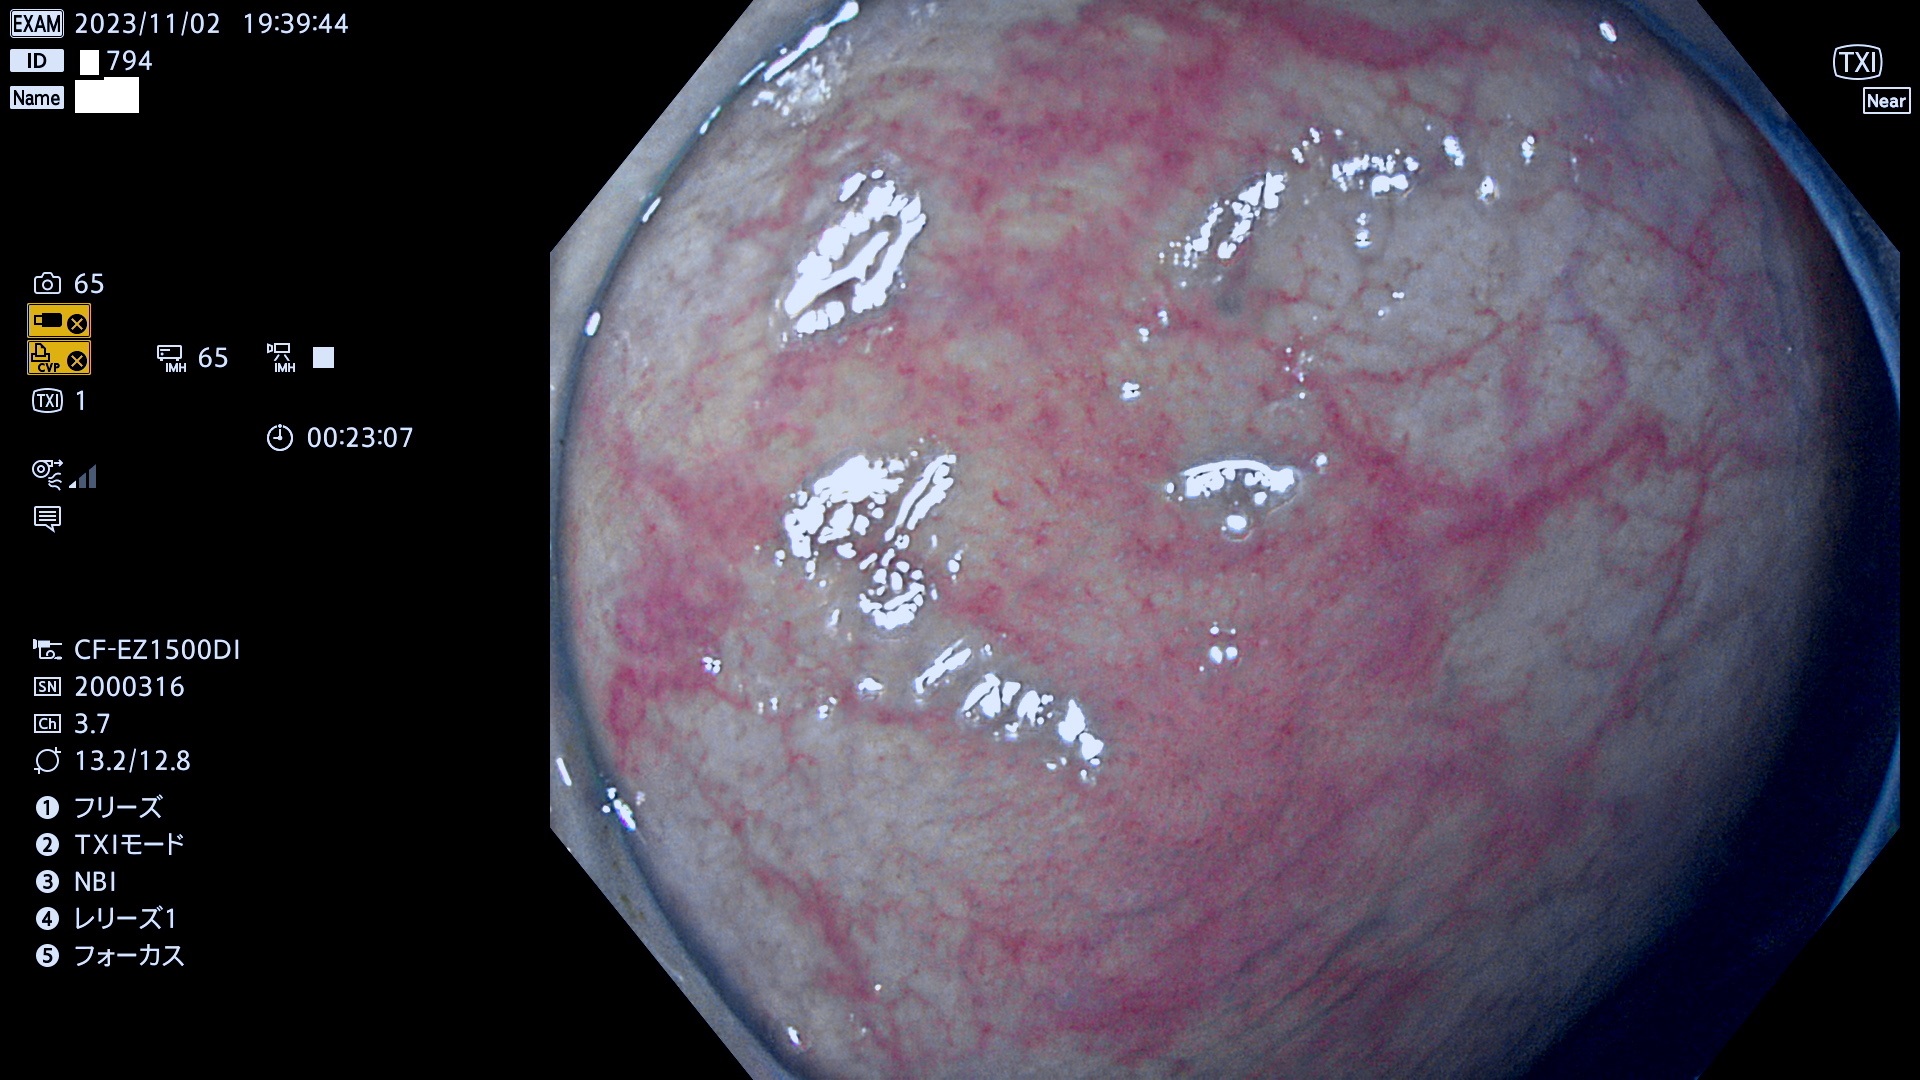

今週のUb、Uc型腺腫

表面型腺腫(Flat Adenoma)の中で、完全に平坦な物をUb、陥凹している物をUcと呼びます。平坦隆起型(Ua)よりも、発見が難しく危険な病変です。このタイプは「内視鏡後・大腸癌の重要犯人」であり、この発見率は「腺腫発見率」よりも、重要な意味があります。

毎週の検査(木・金・土・日)に発見されたUb、Uc型・腺腫を、その週の日曜の夜にUPし1週間、提示します。

抽出の対象期間 2023年11月2日(木)〜11月6(月)の5日間(60件の検査)11件